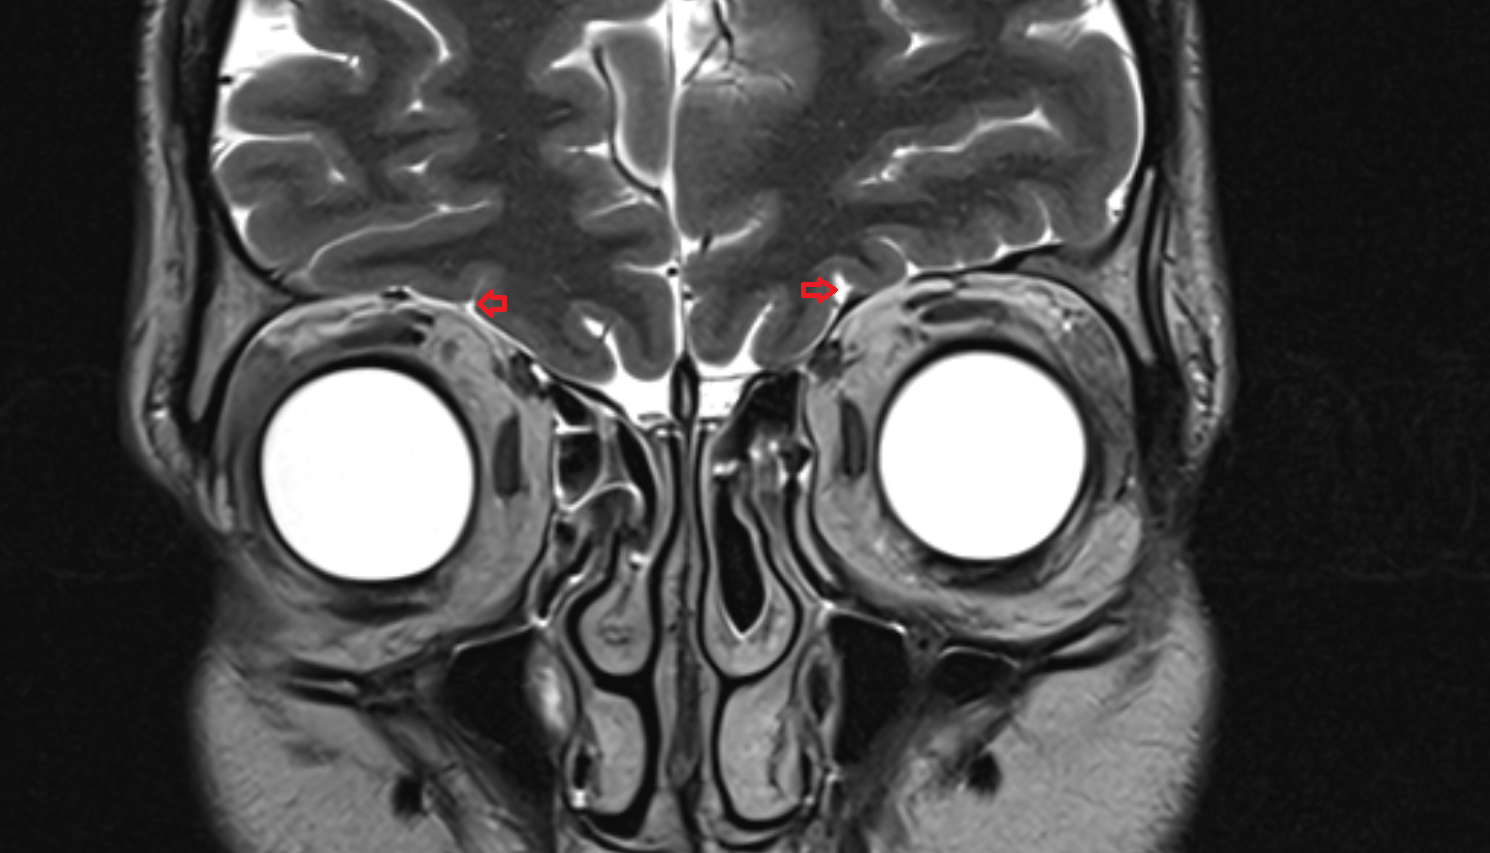

- Optic Nerve (Cranial Nerve II)

- Orbital part of optic nerve

- Optic nerve sheath

- Subarachnoid space of optic nerve